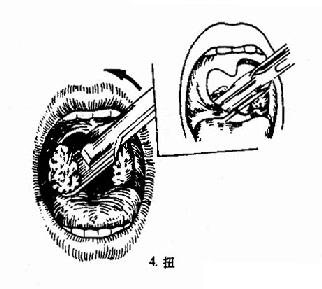

(二)挤切法(guillotine method)(图6-3):

2.操作:病人取仰卧或坐位,助手将其头部固定,置入开口器后,手术者以压舌板压舌,暴露扁桃体下极,右手持挤切刀,从扁桃体下极套入,再转动刀环,使其位于扁桃体和咽腭弓之间,将扁桃体后面及上极套入,并向舌腭弓方向提起,这时扁桃体在舌腭弓下隆起成一“包块”,即用左手拇指或食指将“包块”挤压入环内,随即收紧刀柄,推动刀杆前进,使刀片切入刀环的尽端,以迅速有力的扭转及提拔动作切下扁桃体。以同法切除对侧扁桃体。助手迅速将患者头部侧转,使其将血吐出。止血方法同剥离法。

图6-3 扁桃体挤切术